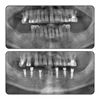

Implant Treatment